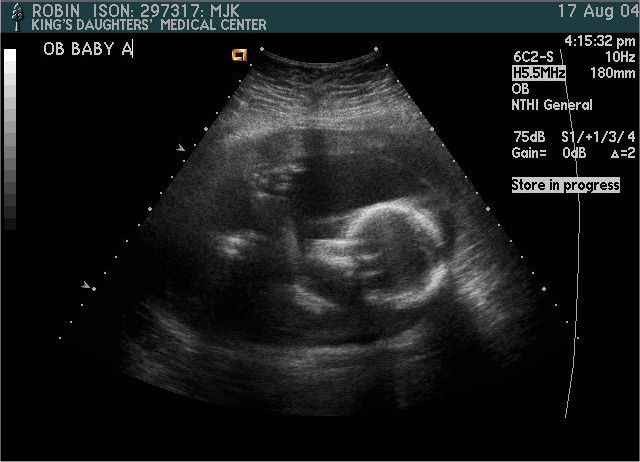

Baby A

Pictures from Ultrasound at 20 weeks.